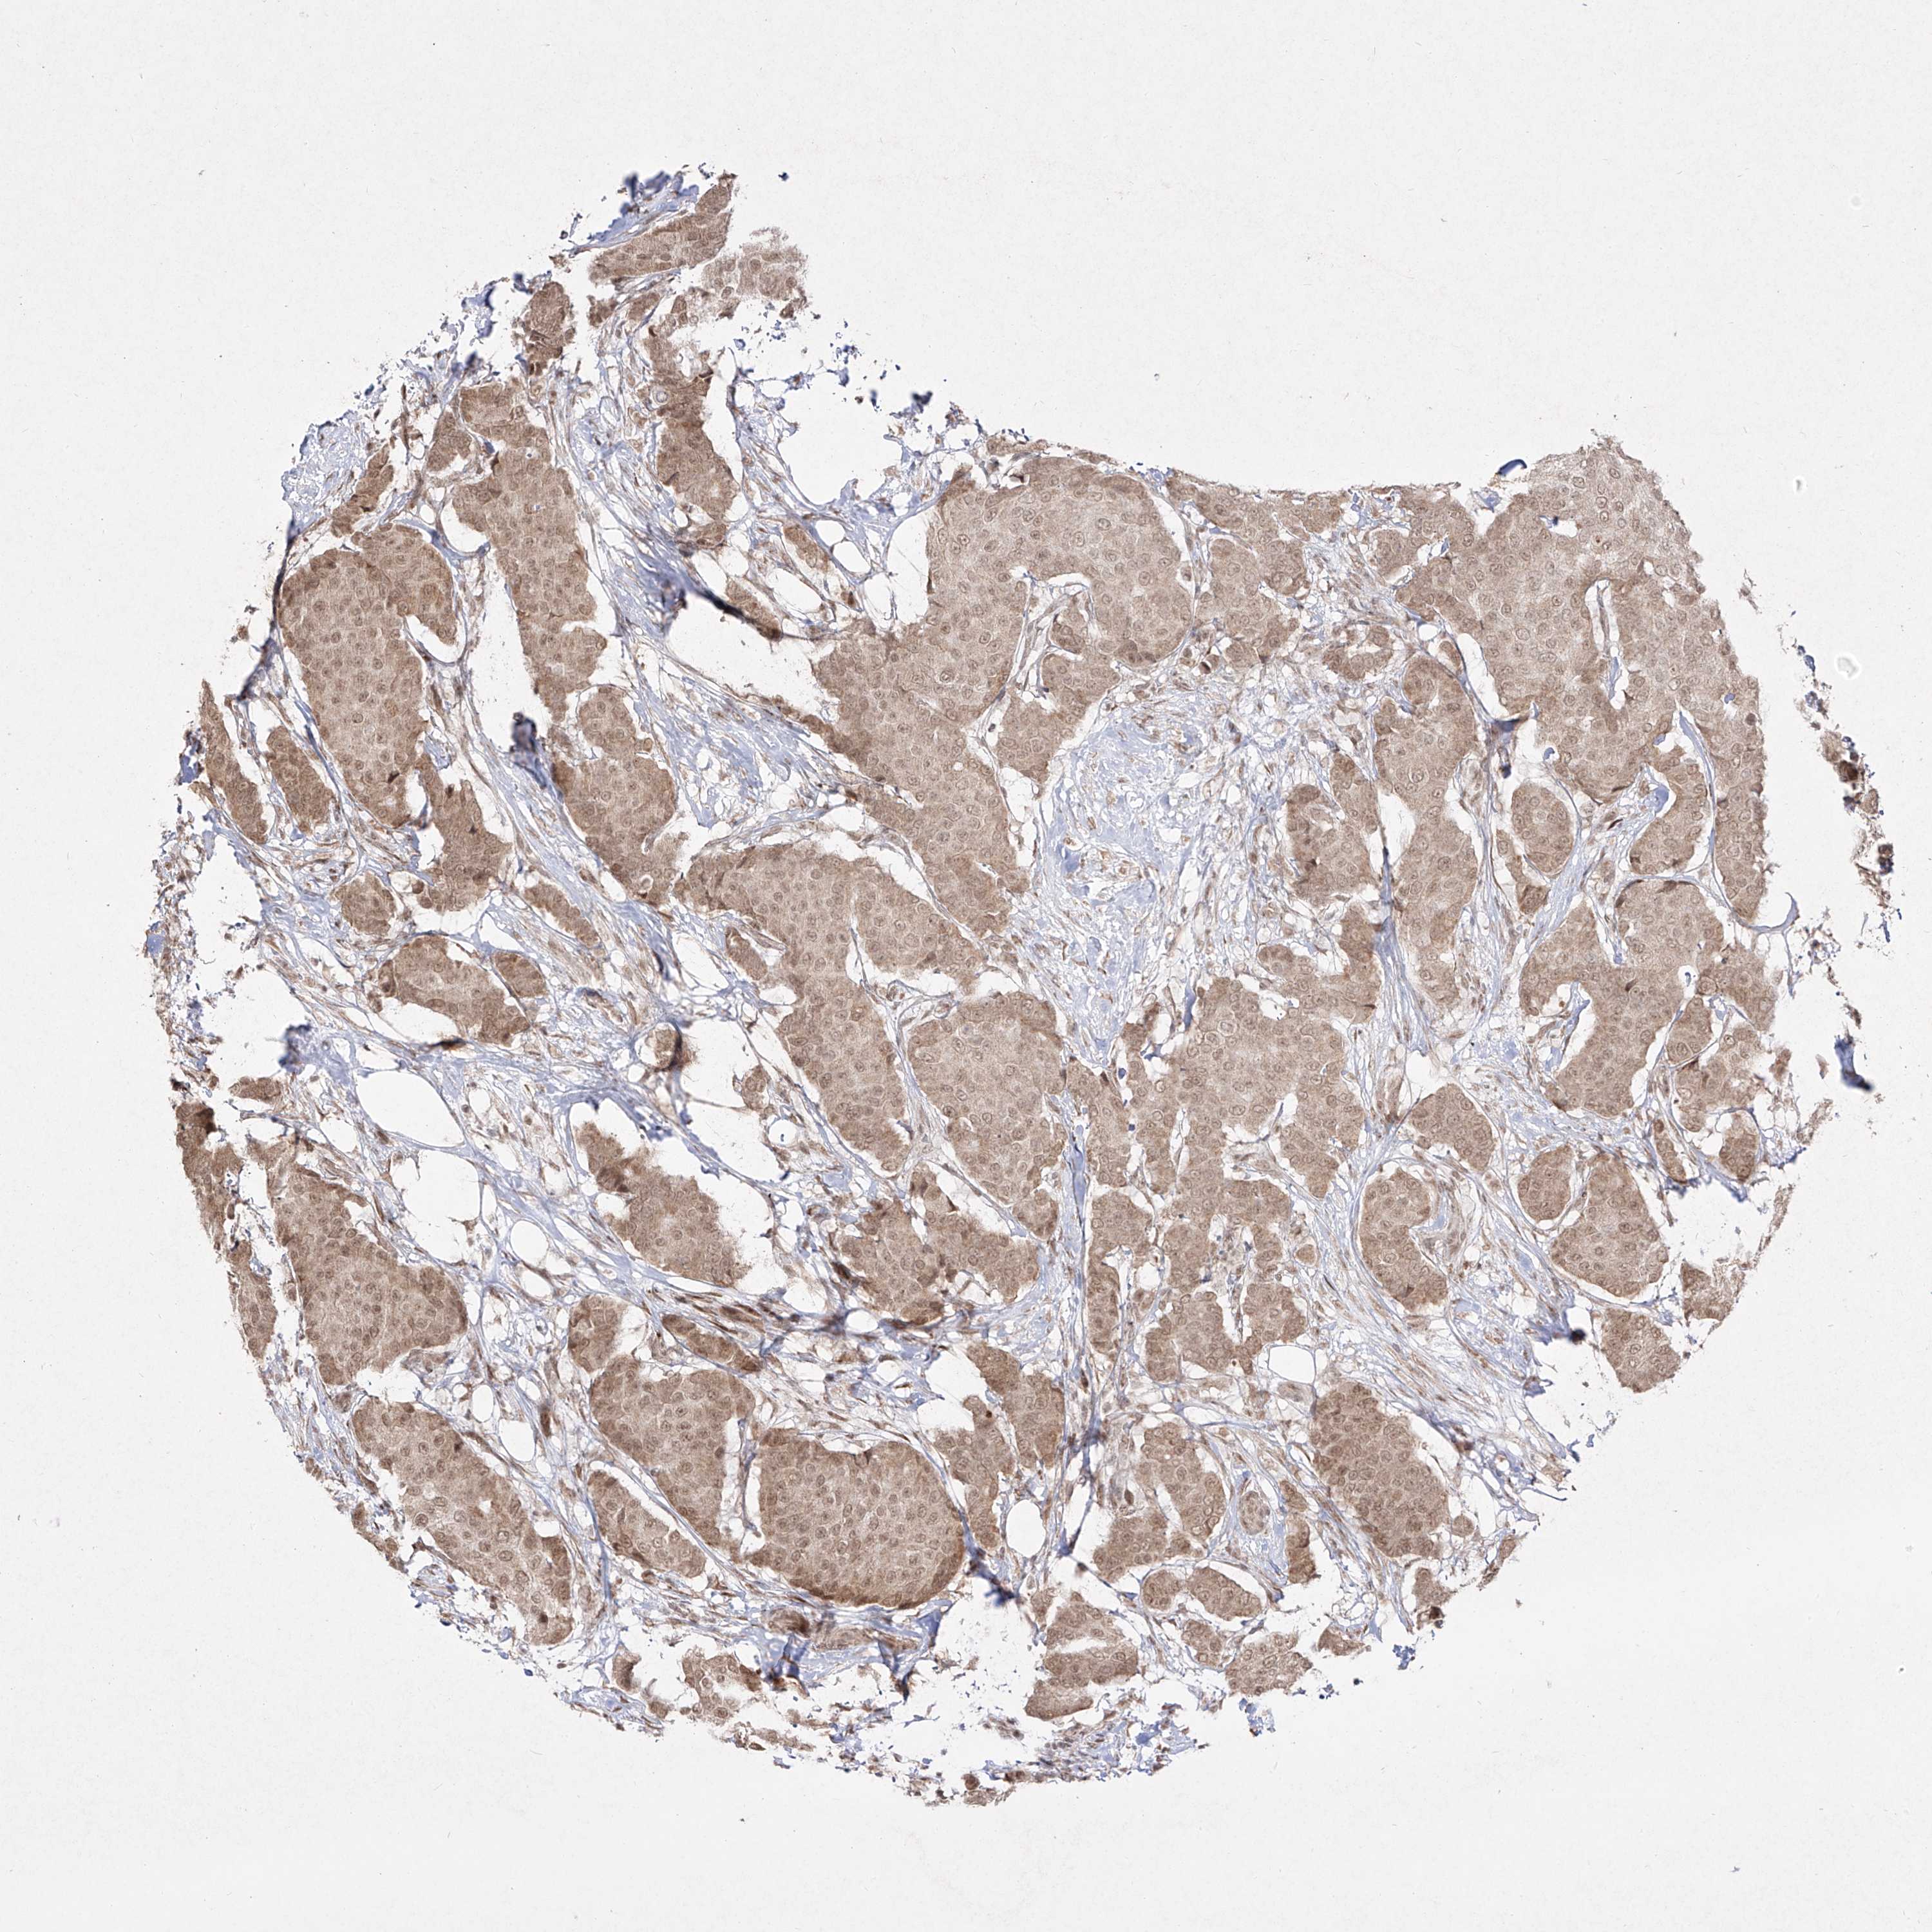

CANCER BREAST CANCER Show tissue menu

BRCA TCGA BRCA VALIDATION PROTEIN EXPRESSION

Breast cancer

Human cancer